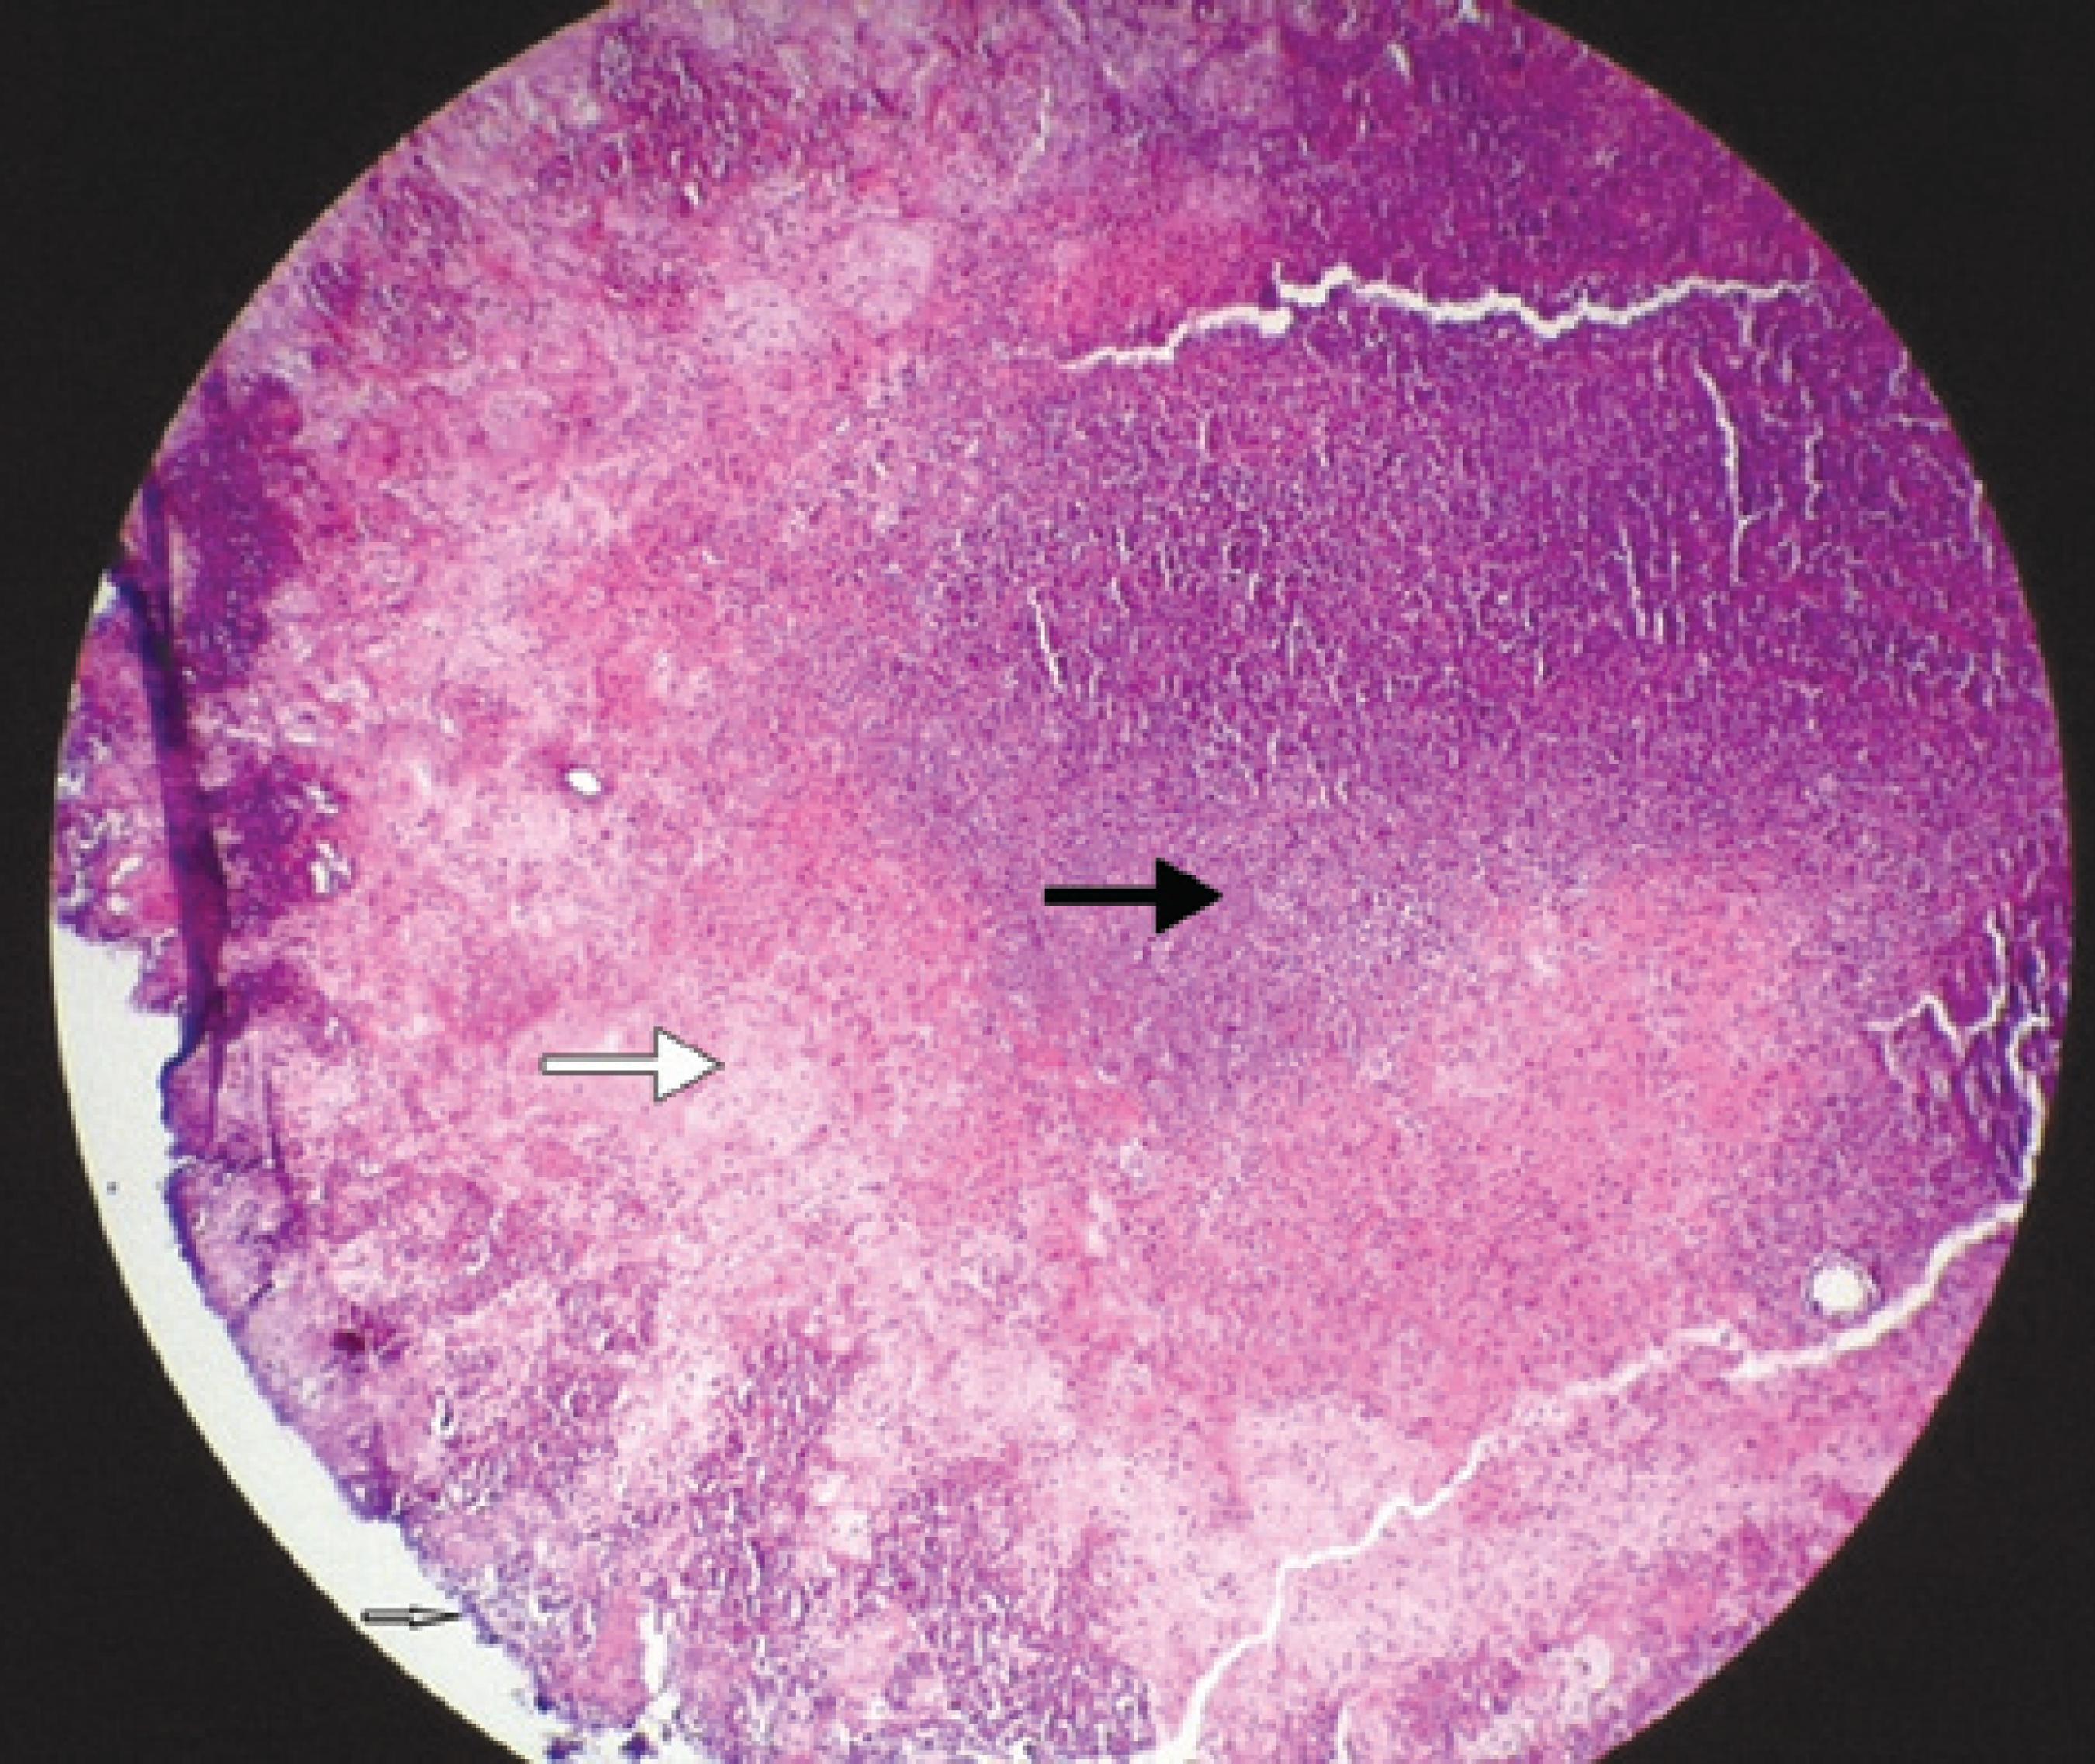

We excised the conjunctival membranes and administered topical netilmicin preservative-free eye drops (SIFI S.P.A, Italy) 4 times daily, sodium hyaluronate preservative-free eye drops (SIFI S.P.A, Italy) 4 times daily, and dexamethasone ointment (Alcon Couvreur, Belgian) 2 times daily for the first two postoperative days. Serological and microbiological examinations for cytomegalovirus, Epstein-Barr virus, human immunodeficiency virus, rubella virus, Toxoplasma gondii, mycoplasma pneumonia, Chlamydia trachomatis, Treponema pallidum, and Corynebacterium diphtheria were negative. Her blood group was O positive. Histopathological examination of the excised conjunctival membranes exhibited a massive fibrin exudation with a disrupted epithelium, inflammatory cellular infiltration, and moderate leukocyte infiltration (Figure 2), confirming ligneous conjunctivitis. All clinical signs and her family history indicated plasminogen deficiency. We measured her plasminogen activity at 24% (normal range, 80%-120%); her aunt's and cousin's plasminogen activities were 16%.

Figure 2 Histopathology of the conjunctival membranes (white arrow: disrupted epithelium; large white arrow: massive exudation of fibrin; black arrow: inflammatory cellular infiltration).